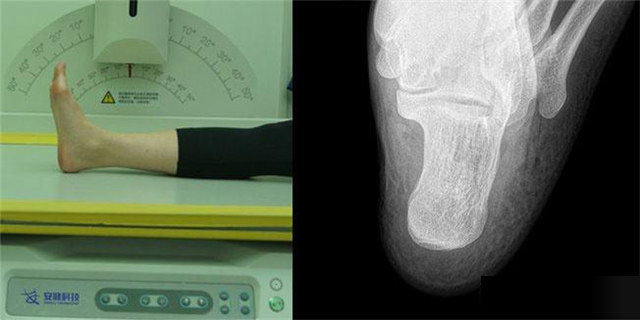

下肢:脛腓骨、踝、足脛腓骨長骨檢查需要包括--側的關節踝關節常規正+外側位,特殊時可選內斜位足常規前後正位+內斜位,外傷鑒定等情況,需要負重的水平側位(包括足尖和足跟)跟骨側位+軸位